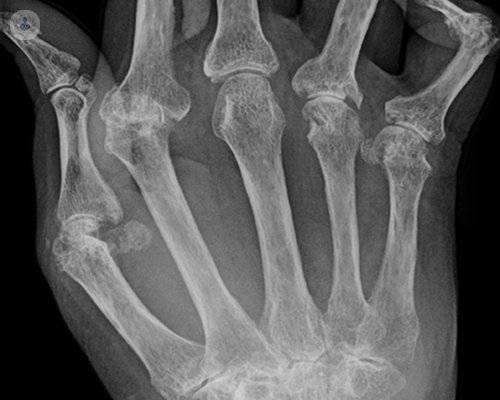

• artritis-reumatoide-en-manos

Fármacos biológicos, tratamiento eficaz para frenar el avance de la artritis reumatoide

La artritis reumatoide es una patología inflamatoria crónica que se engloba en las enfermedades autoinmunes y que afecta a las articulaciones. La Dra. Vela, reumatóloga, explica que, aunque es compleja, el pronóstico actual puede ser bueno, consiguiendo evitar la incapacidad del paciente.